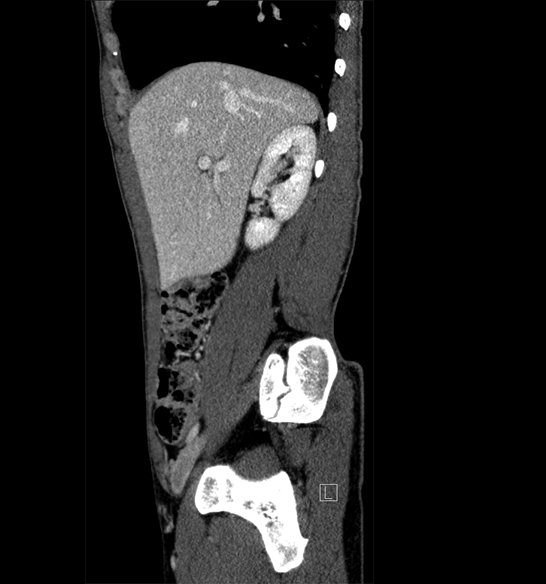

Body

Covers abdominal CT anatomy.